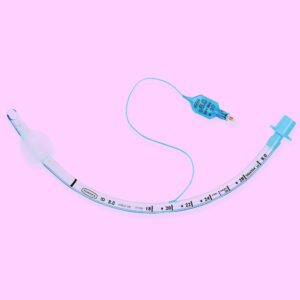

- Tracheal tube

Tracheal intubation in advanced life support

Laryngoscopy and intubation of the trachea should not last longer than 30 seconds. Any doubt about the correct placement of the tube in the trachea leads to tube withdrawal and re-oxygenating the patient before further attempts.

Tracheal intubation advantages

- Allows ventilation with up to 100% oxygen

- Isolates airway, preventing aspiration

- Allows suction of the airway

- The release of a resuscitation team member